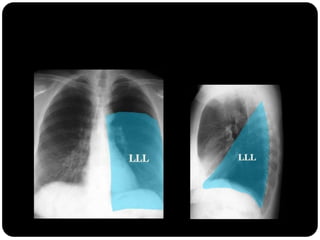

Atelectasia do lobo

inferior esquerdo

Atelectasias de lobos

inferiores deslocam

o hilo posterior e

medialmente;

Ateloectasia do lobo

Atelectasia do LIE

 Atelectasia LIE:

 Opacidade triangular na área retrocardíaca

em incidência frontal;

 Fissura oblíqua deslocada mais

posteriormente e rodada em orientação

mais sagital do que a orientação coronal

normal;

 Ligamento pulmonar inferior: folha de

tecido conjuntivo/ pleura visceral e parietal

fundidas  ligação do LI ao mediastino;

Se estende do hilo até o diafragma;

TC: pequeno bico de pleura mediastinal

dirigido lateralmente;

responsável pela configuração triangular e

colabamento medial do LIE;